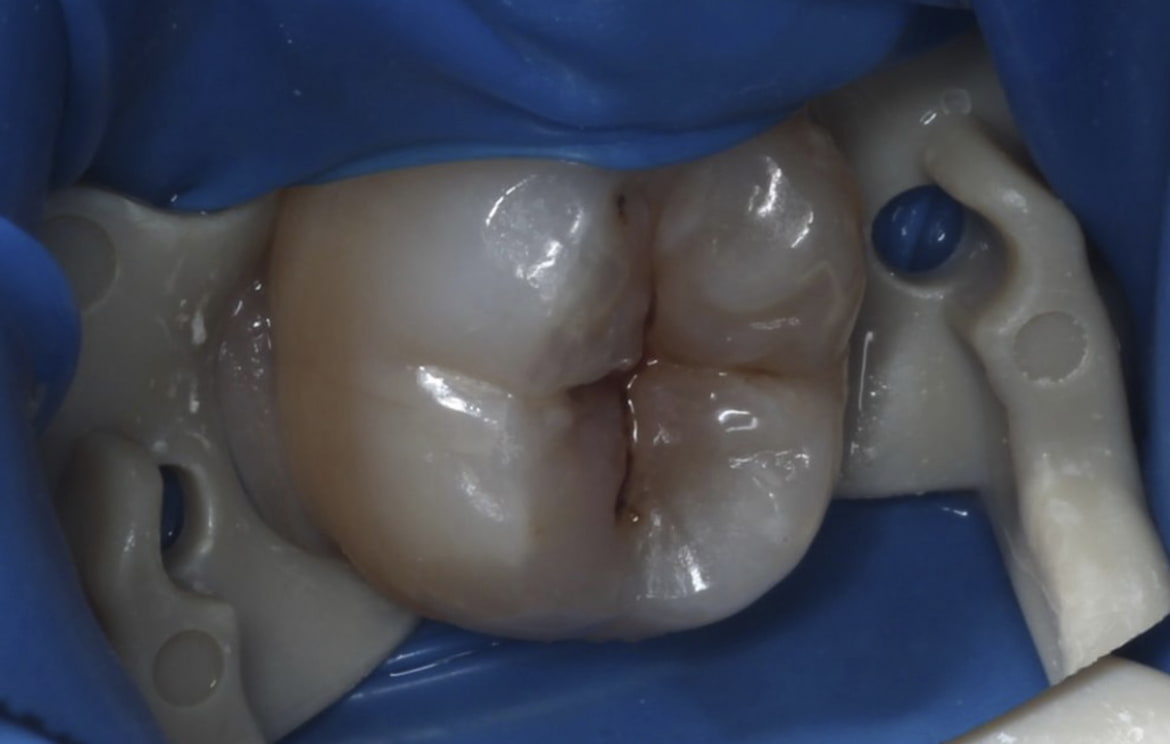

Наши работы